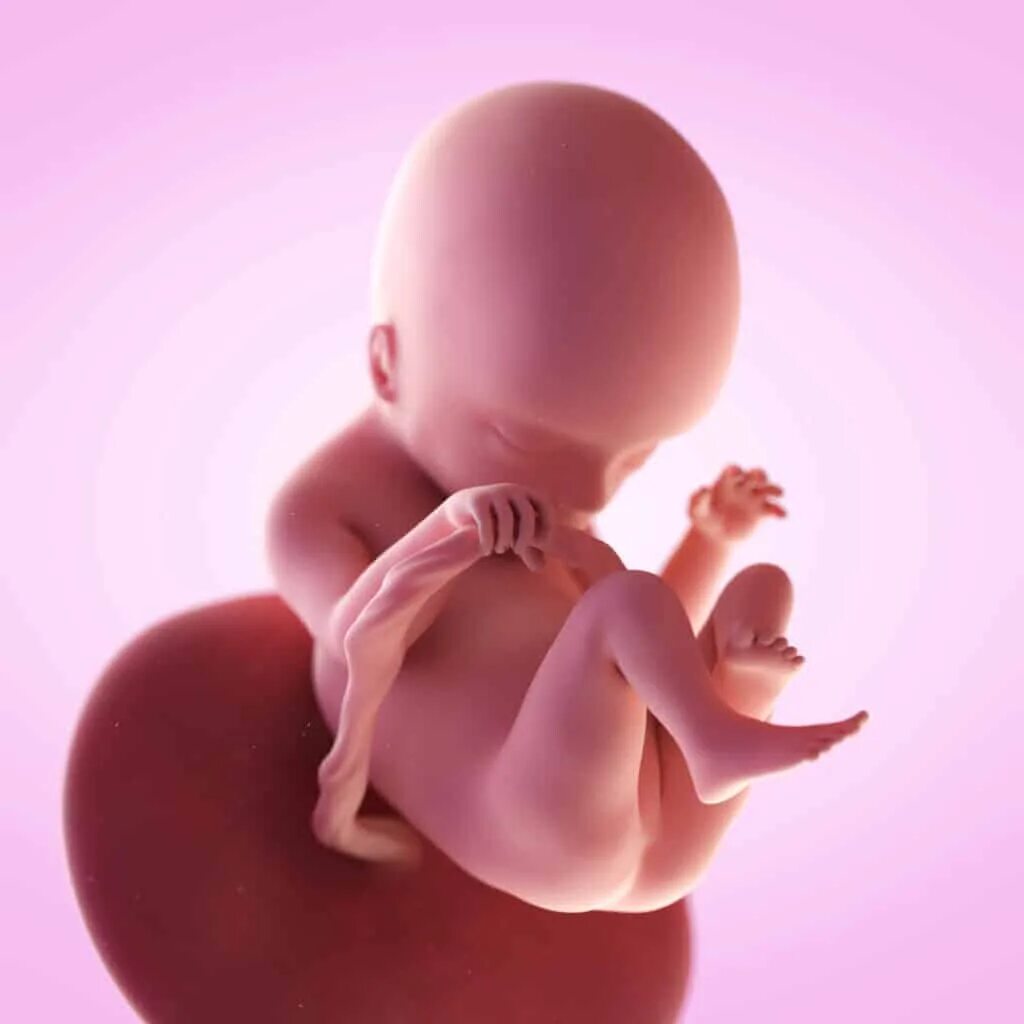

Как выглядит ребенок в 18 недель